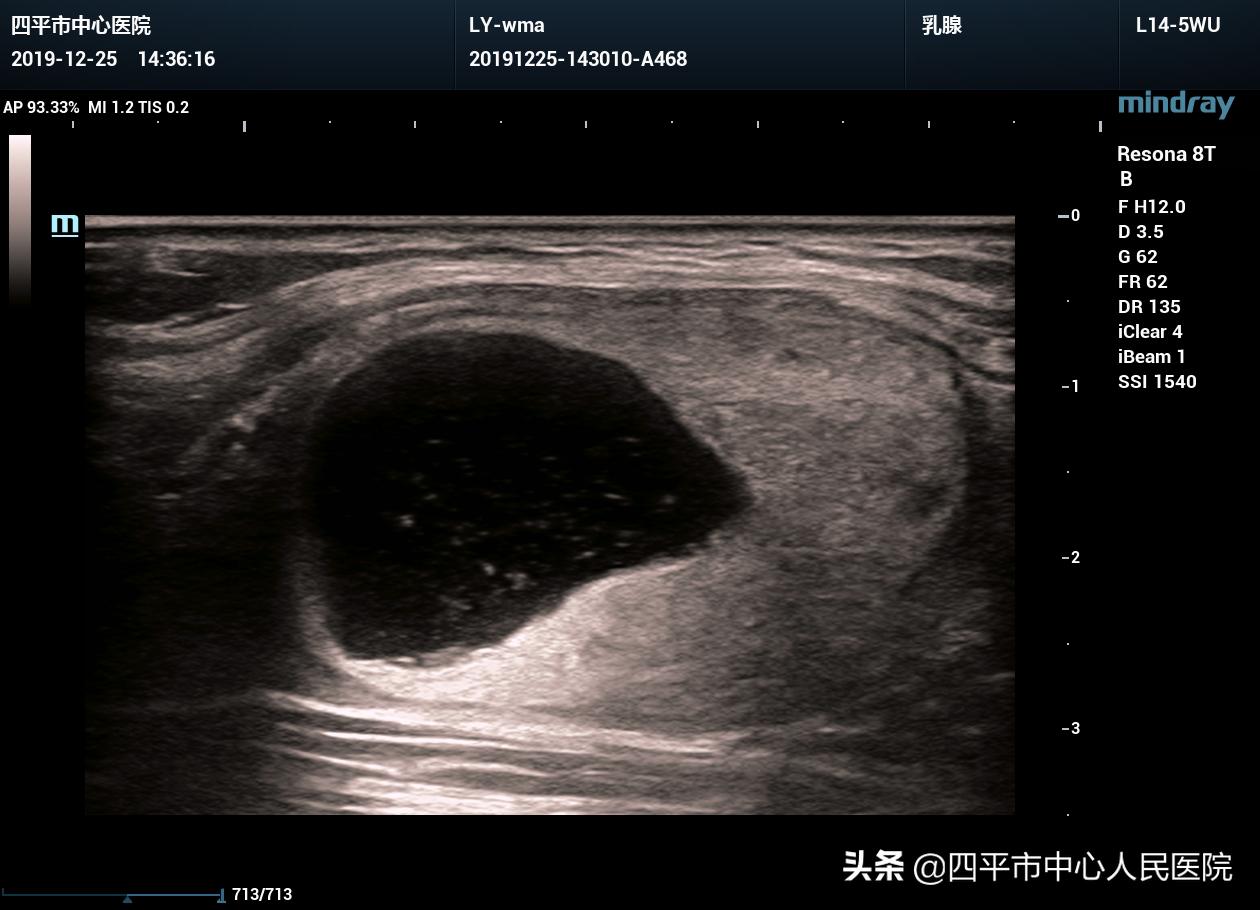

常规超声所见:甲状腺左叶见大小约4.0×2.6×2.8cm囊实混合性结节,以实性回声为主,边界清晰,形态规则,纵横比<1,CDFI:实性回声内及结节周边见血流信号。

超声提示:甲状腺左叶囊实混合性结节,TI-RADS 3级。